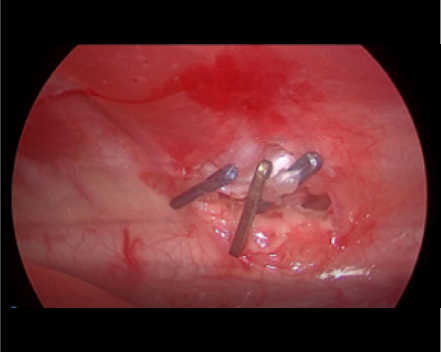

腹腔鏡を用いた副腎腫瘍摘出術